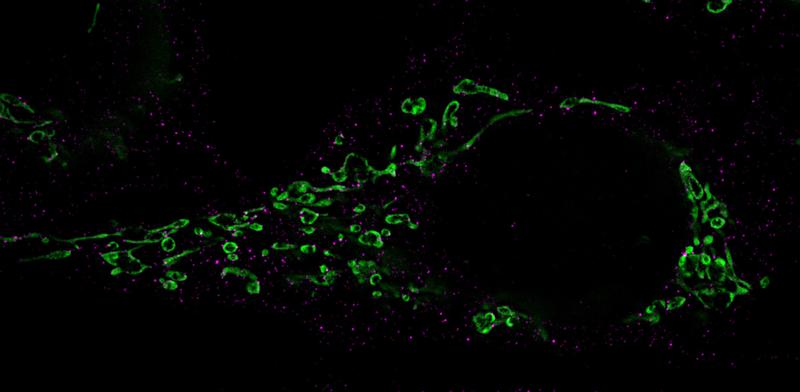

Die regulatorische miR-aU14 stammt vom Virus selbst. Sobald sie exprimiert wird, greift sie in den Stoffwechsel der menschlichen Mikro-RNAs ein. Dabei stört sie selektiv die Reifung gleich mehrerer Mikro-RNAs aus der miR-30-Familie. In der Folge werden diese wichtigen zellulären Mikro-RNAs nicht mehr gebildet, und das wiederum beeinflusst einen zellulären Signalweg, die sogenannte miR-30 / p53 / Drp1 Achse.

Über diesen Weg induziert die virale miR-aU14 die Zerstückelung der Mitochondrien. Diese Zellstrukturen sind von zentraler Bedeutung für die Energieproduktion, aber auch für Signalübertragungen bei der Abwehr von Viren.